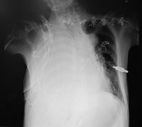

2019年10月患者无明显诱因出现发热、呼吸困难,伴咳嗽、咳痰,喘憋症状进行性加重,端坐前倾位可稍缓解,先后就诊于呼吸科和血液科,胸片提示右侧大量胸腔积液(图2)。外周血HIV(-),巨细胞病毒(-),EBV(-)。胸部CT示右侧胸腔积液伴右肺下叶部分肺组织膨胀不全,新出现;纵隔及两侧肺门多发淋巴结影,部分较前稍增大;心包少量积液为新出现;肝脏形态饱满,脾脏在最大横断面水平相当于第8肋。行胸腔穿刺置管引流术,胸水常规:单个核细胞81.2%,RBC 5 860/mm3,WBC 953/mm3,比重1.021,李凡他实验阳性;胸水生化:葡萄糖4.6 mmol/L,白蛋白17 g/L,LDH 1 373 U/L,腺苷脱氨酶128.9 U/L;胸水病理回报:符合原发渗出性淋巴瘤(图3),免疫组化:HHV-8(+),CD20(-),CD3(少量+),MUM1(+++),Ki-67(80%+),C-myc(70%),P53(20%+),CD138(-),CD30(+++),ALK(-),PAX5(-),CD79A(-),CD38(-);原位杂交EBER(+);胸水FISH:MYC、BCL-2、BCL-6、CCND1未见分裂象;TP53未见突变。结合患者临床表现(以胸腔恶性渗出为主且不伴明显肿块)及病理结果,诊断为PEL[7]。患者合并全血细胞进行性减少、Ⅰ型呼吸衰竭、DIC、肝功能衰竭、急性肾损伤,入院后予对症支持抗感染治疗及无创呼吸机辅助呼吸,病情仍进行性恶化,结合病理诊断,在强效抗感染的同时予地塞米松5~10 mg/d治疗,后因原发病进展迅速,患者出现阵发性房颤、低血压,2019年11月11日抢救无效死亡。

本病例发生于胸腔,表现为右侧大量顽固性胸腔积液及呼吸困难,未检测到明显肿块。HHV-8(+),B细胞标志物表达均为阴性,浆细胞相关抗原:CD30(+),CD38(-),CD138(-),原位杂交EBER阳性。与大量文献报道中不同的是,该患者HIV阴性,是较少见的HIV阴性PEL,仅见于个案报道[2,10,11]。这些HIV阴性病例通常存在如下特征:高龄、地中海起源、EBV阴性及不完全是男性或男性同性恋患者[12]。但与同类报道不同的是,患者为MCD治疗后发生的HIV阴性PEL,是国内首例。既往MCD、多疗程化疗史、激素治疗史及高龄可能是其存在免疫缺陷进一步潜伏感染HHV-8导致PEL的原因。有研究报道了MCD与PEL的关联,可能提示MCD患者发生PEL的风险更高[13]。因此,在今后的临床工作中,对于既往存在MCD的患者,新出现胸腔、心包腔、腹腔恶性渗出,即使HIV阴性,除原发病进展外,我们还需考虑PEL可能,进一步完善积液的病理学检查以明确诊断。